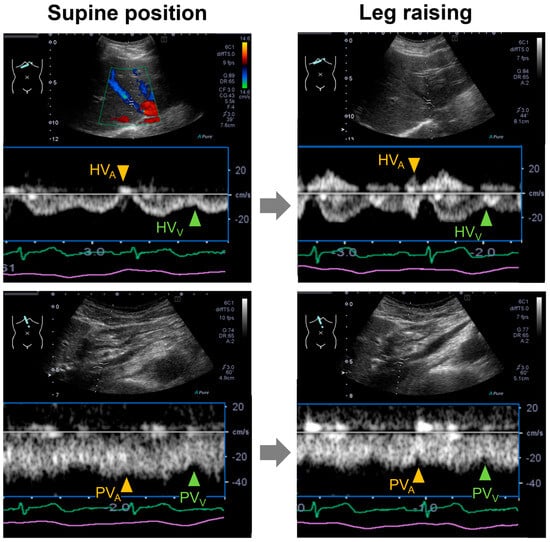

| IVC diameter during expiration (mm) | 18 ± 5 | 13 ± 3 | <0.001 |

| IVC respiratory change (%) | 60 ± 9 | 65 ± 11 | 0.050 |